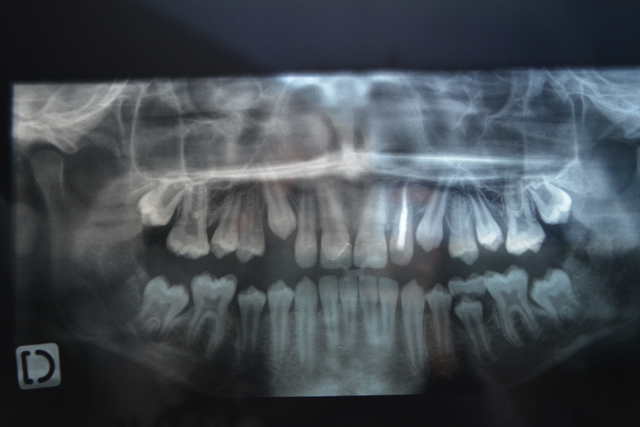

Nous sommes à 16 mois.

Je viens juste de recevoir une radio du confrère fort aimable qui le suit en métropole.

Il suspecte un début d'ankylose et aussi un début de rhizalyse. Un moyen pour détecter et valider l'ankylose?

Normalement l'ortho devrait démarrer dans quelques mois.